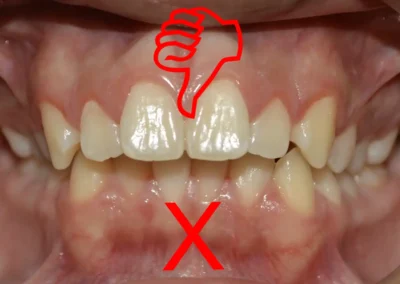

Indicar ortodoncia solo porque los dientes no están alineados es un error frecuente. La alineación por sí sola no define la necesidad de tratamiento.

Antes de cualquier indicación, es imprescindible evaluar el estado periodontal, la calidad del hueso de soporte, la presencia de patología activa, el nivel de higiene del paciente y la relación de la mordida con el resultado final esperado.